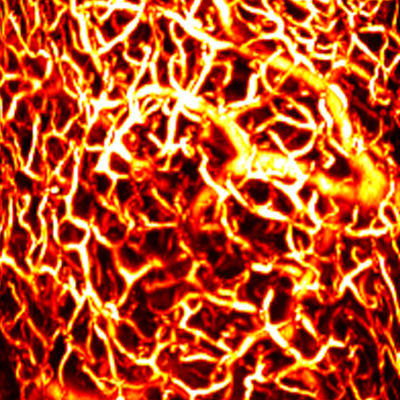

MAP

Cross sectional view

Surface(Depth) view